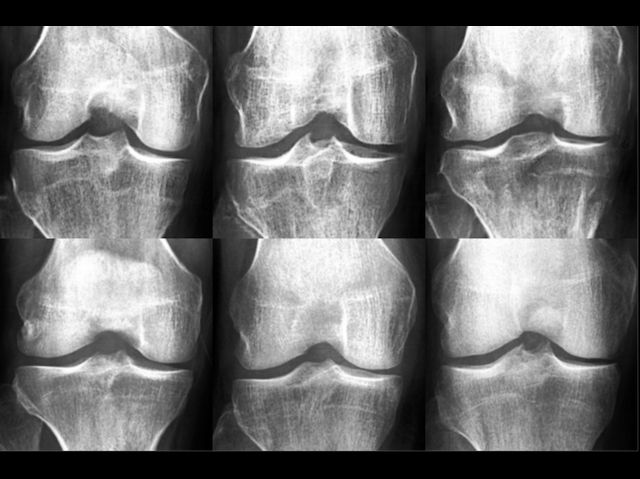

The x-rays of osteoarthritic human knees on the top row are entirely fake – a research team generated them using an artificially intelligent algorithm – while those on the bottom row are genuine. Or, wait, is it the other way around? The point is, it’s impossible to tell, even for medical experts. Why have scientists gone to the effort of creating fake X-rays, you might ask. Rest assured, there’s more to it than simply trying to fool orthopaedic doctors. Having access to large amounts of patient data can be extremely useful for developing diagnostic, classification, and educational tools, but sharing genuine medical data can be a highly bureaucratic process. The idea, then, is that if AI can generate fake data of such high quality as to be indistinguishable from real patient data, it could be used to help build valuable tools without the hassle of untangling all the red tape.